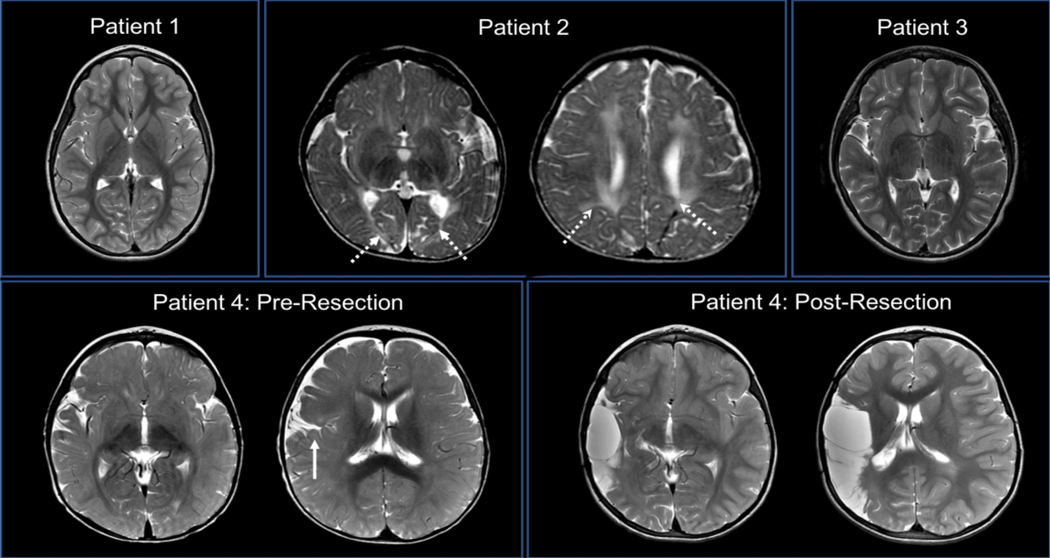

These cases suggest that pediatric epilepsy patients with dysfunction of the opercular cortex may be at increased risk for developing lacosamide-induced dyskinesias. The operculum includes the motor cortex responsible for control of the face and mouth. Pathology in this region can lead to the well-established opercular syndrome, characterized by loss of voluntary facial musculature control but preservation of automatic-emotional movements.4,5 Three of our patients had seizure semiology suggesting opercular onset – including hypersalivation, facial twitching, and choking – and the fourth patient had perisylvian pathology (Figure 1) and opercular resection. The opercular region contributes to movement control through the cingulo-opercular circuit, which is postulated to play a role in motor task maintenance. Together with fronto-parietal circuits, these complex motor networks are uniquely linked in children compared to adults,6 and dysregulation and/or immaturity of these circuits has been implicated in complex movement disorders. For example, it is postulated that abnormal connectivity with and within the cingulo-opercular network in children with Tourette Syndrome may lead to impaired suppression of unwanted behaviors such as tics.7 Impaired inhibition of a number of different motor circuits has been implicated in various movements disorders of childhood.8 Thus, immaturity coupled with epilepsy-related dysfunction of cingulo-opercular circuitry in affected children may decrease ability to suppress unwanted or unnecessary movements.

Figure 1:

Neuroimaging of the Opercular Region. MRI T2 sequences. Patients 1 (age 8 years) and 3 (age 10 years) had no obvious intracranial pathology. Patient 2 (age 10 months) had periventricular (left image, arrows) and parietooccipital (right image, arrows) white matter injury, but no opercular pathology. Patient 4’s pre-resection scan (age 3 months) found diffuse right hemispheric polymicrogyria (arrow), while the second scan (age 2 years and 8 months) demonstrated the extent of the resection, including the right opercular region.